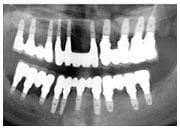

X 光片

全口X光片 治療後